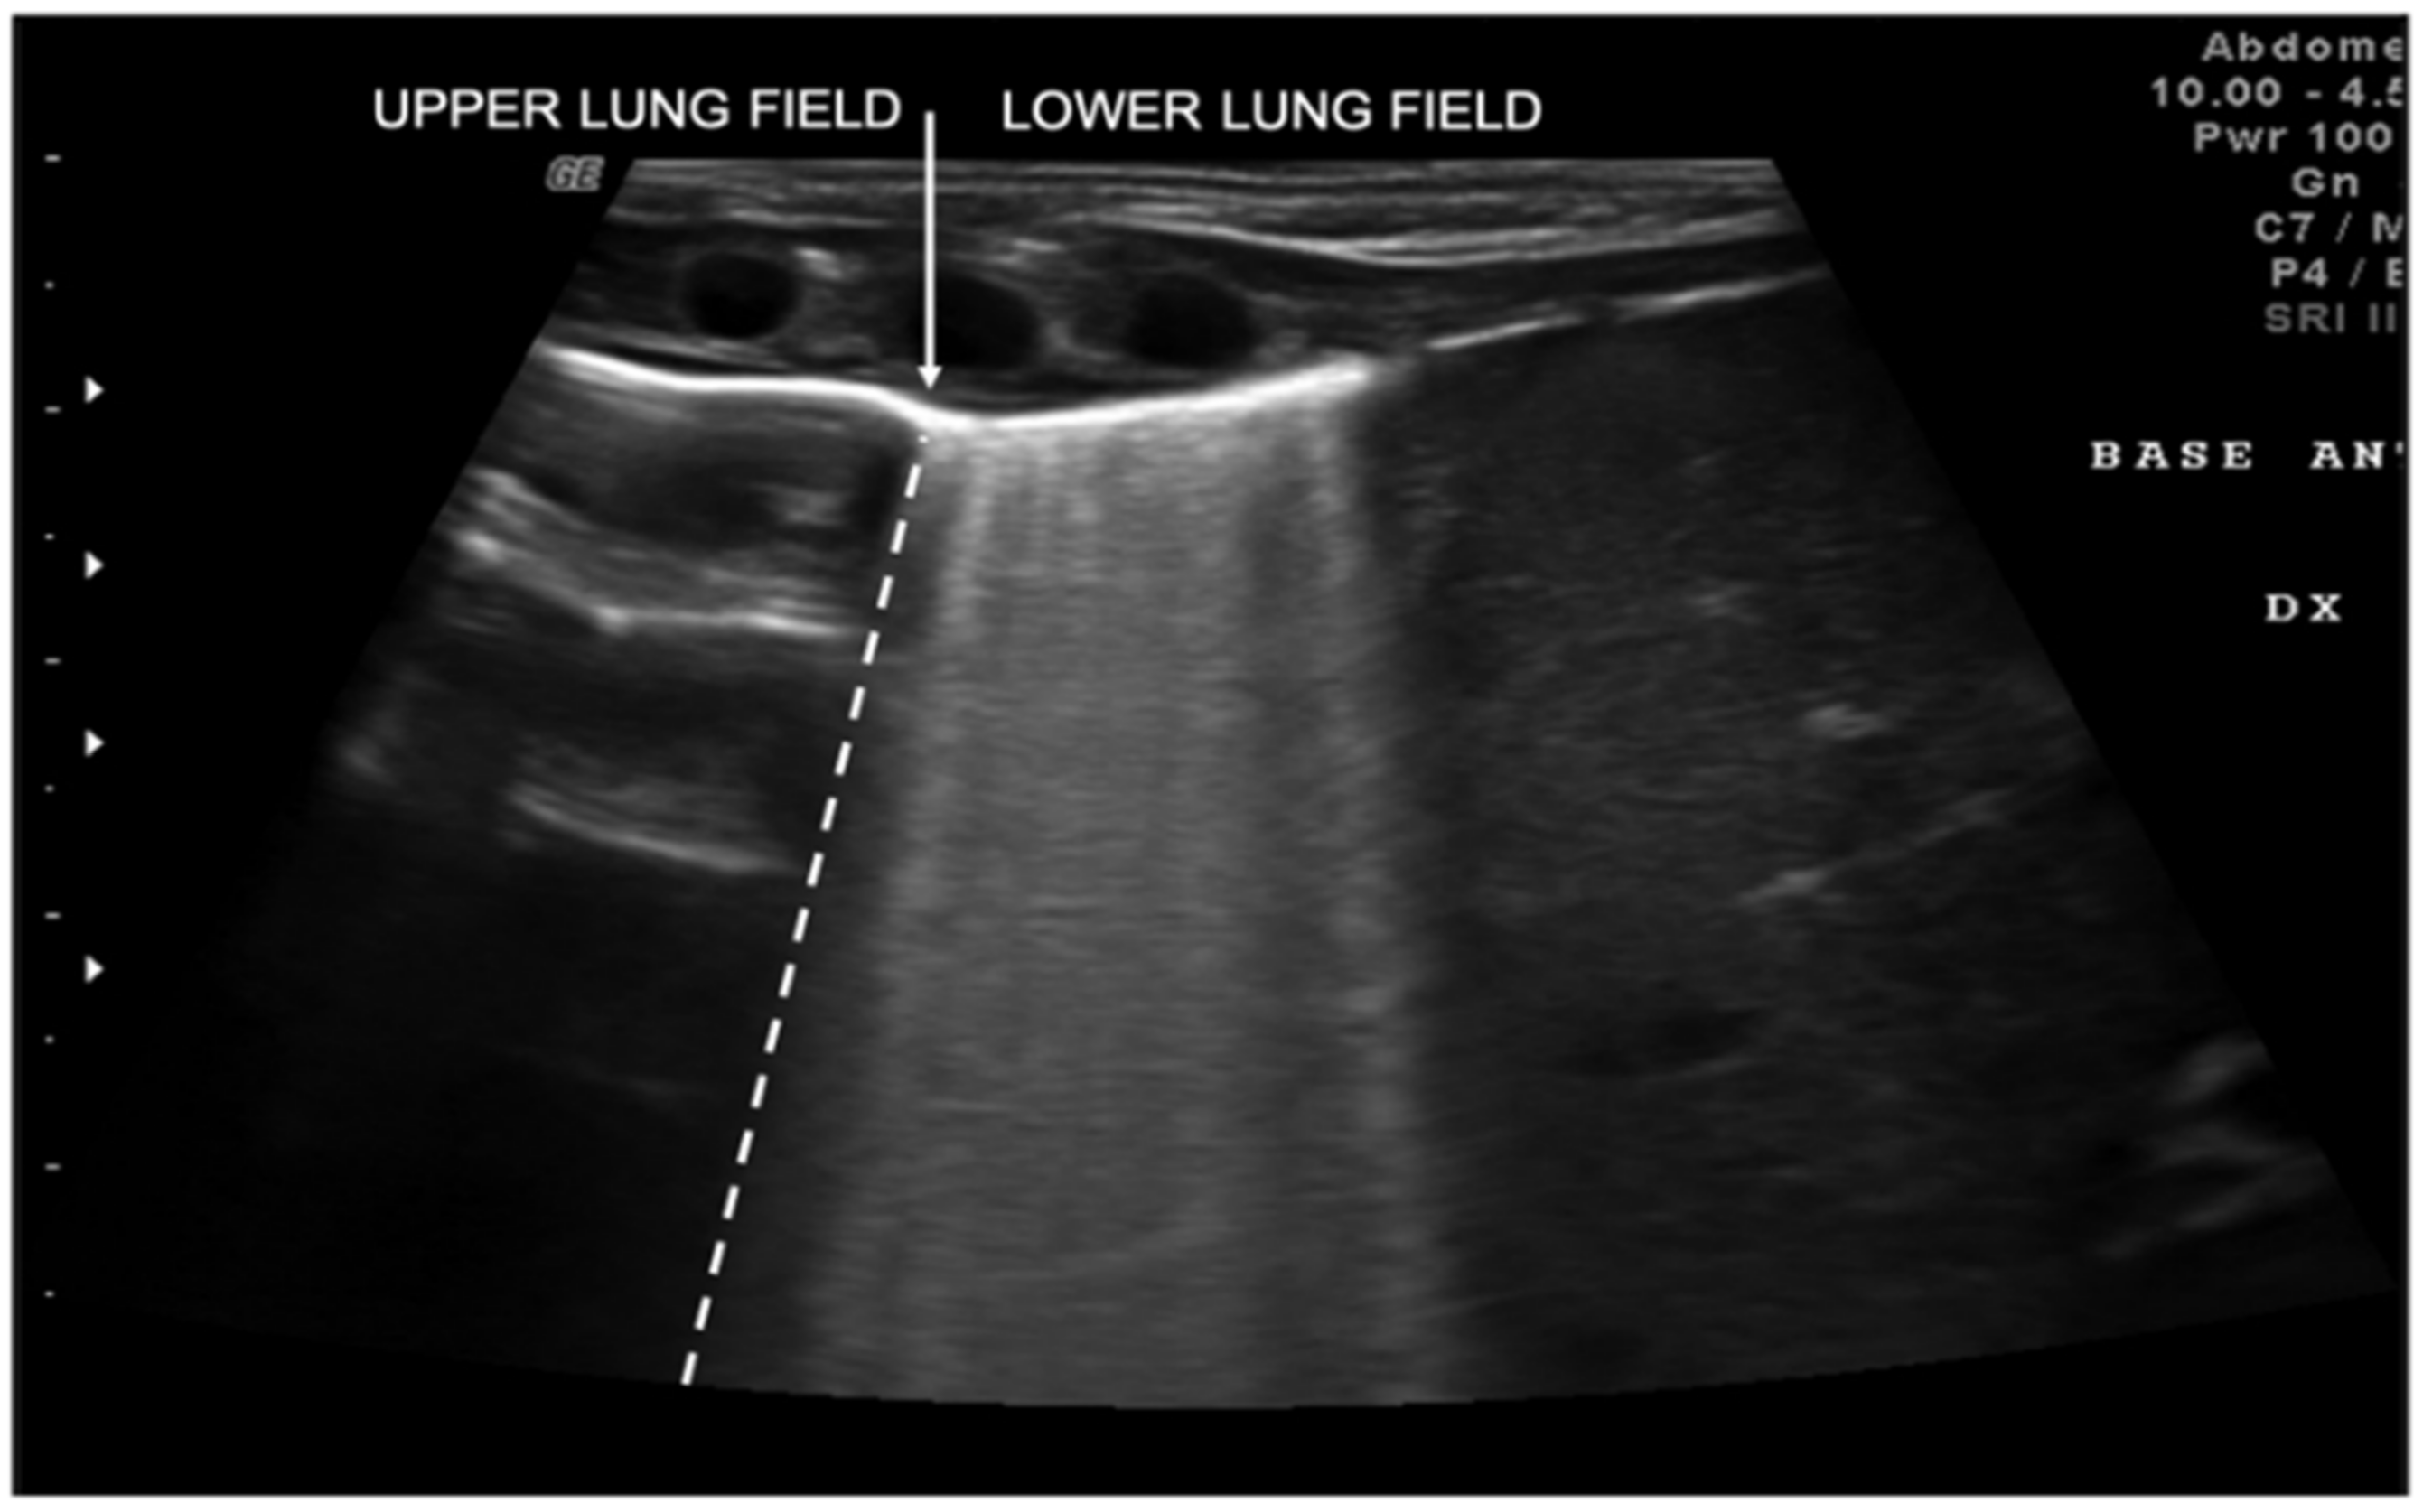

2. Technique and Equipment

3. Lung Ultrasound Findings in Healthy Subjects

5. Neonatal Lung Diseases

- Copetti, R.; Cattarossi, L. The “double lung point”: An ultrasound sign diagnostic of transient tachypnea of the newborn. Neonatology 2007, 91, 203–209. [Google Scholar] [CrossRef] [PubMed]